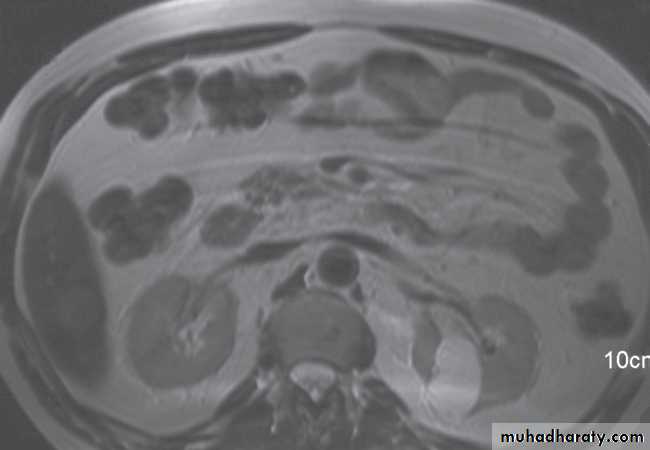

Normal magnetic resonance imaging

As with CT and ultrasound, the renal contours should be smooth. Corticomedullary differentiation is best seen on T1-weighted images and immediately following intravenous contrast enhancement with gadolinium .The renal collecting systems, ureters and bladder are best seen on T2-weighted images, as the fluid returns a high signal intensity .

Some normal variants are well demonstrated on MRI:

-Fetal lobulation & a column of Bertin (which is normal renal parenchyma that may look mass-like) .Special techniques